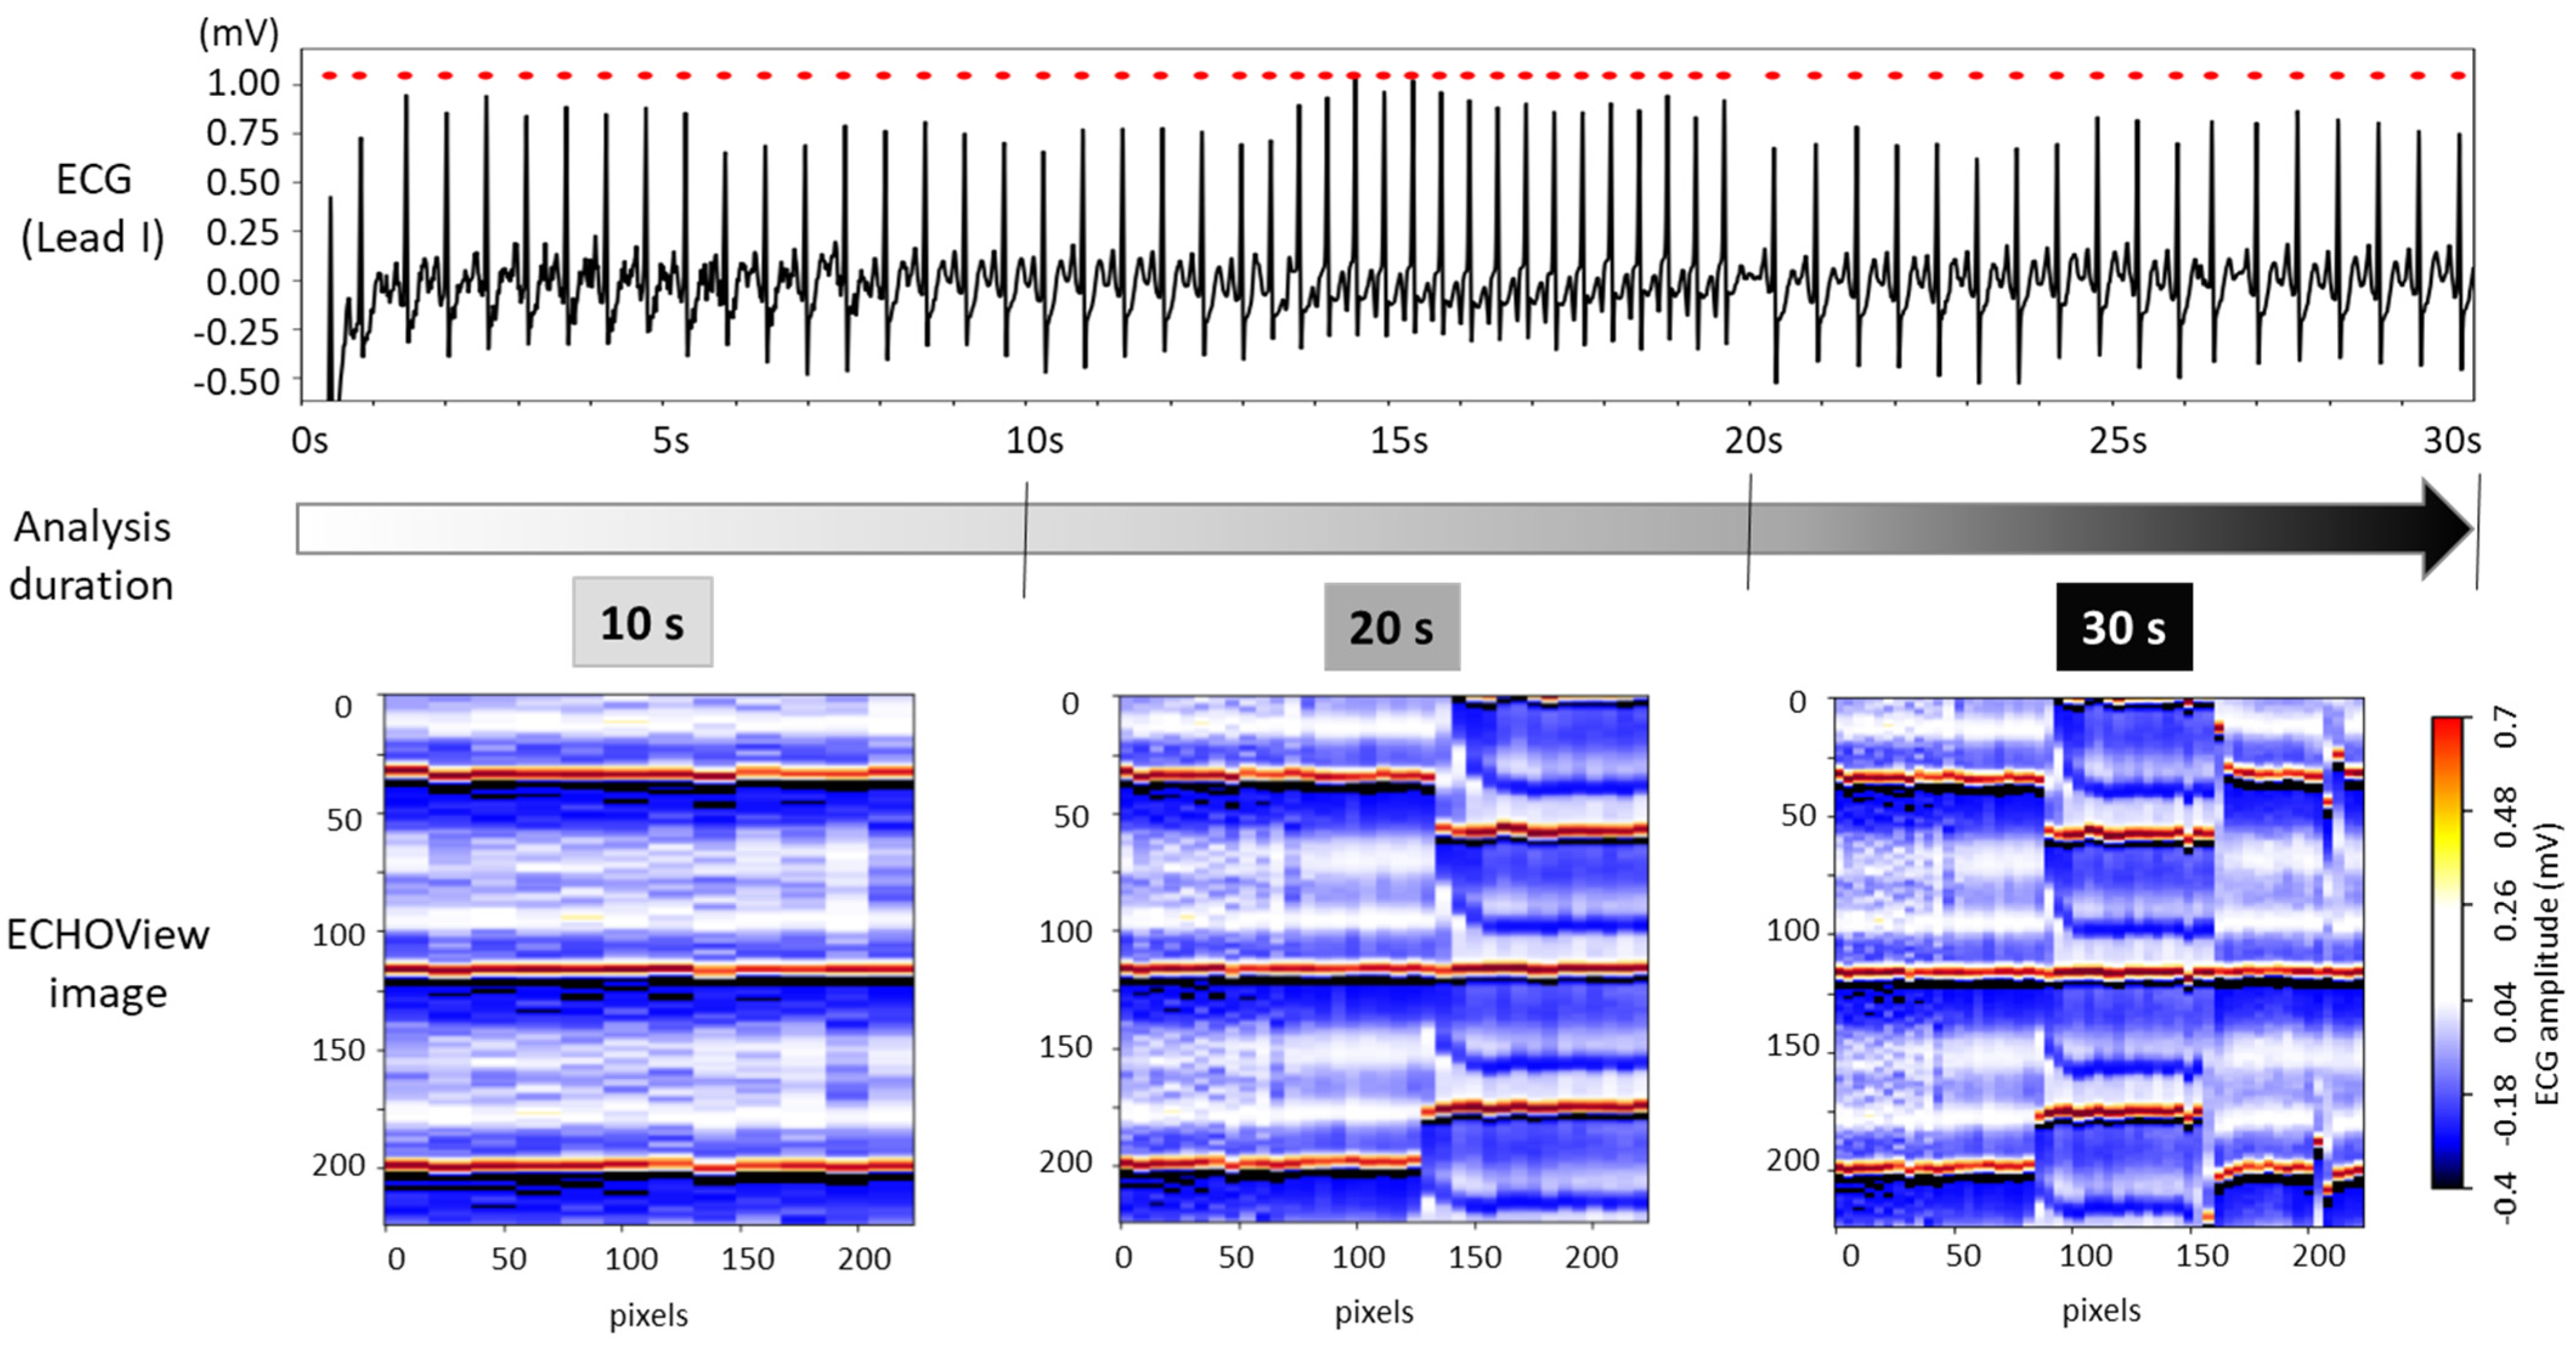

The choice of ECG processing interval duration involves a trade-off between accuracy and decision delay. As illustrated in Figure 8, longer intervals capture more information on rhythm evolution, enhancing reliability but introducing latency. In contrast, shorter intervals allow for faster decisions but may be less reliable due to their limited representation of the ECG rhythm.

Figure 8.

The 30 s ECG trace (top) and corresponding ECHOView images (bottom) generated for analysis intervals of 10, 20, and 30 s.

For this test, ECHOView images were generated for 10, 20, and 30 s intervals while maintaining a consistent colormap. Although the image width varies based on the number of QRS complexes within the analysis interval, all ECHOView images are resized to match the DNN input requirements, as outlined in the flowchart in Figure 2. In Figure 8, the only noticeable difference between the 10, 20, and 30 s ECHOView images is the x-axis granularity (the level of detail or resolution along the x-axis), which is determined by the number of included QRS complexes. The shortest interval (10 s) contains fewer QRS complexes, making individual beats appear wider when the image is rescaled. In contrast, the longest interval (30 s) includes more QRS complexes, leading to finer granularity, where individual beats are more compressed but provide a broader view of rhythm variations over time.

This test applies the same image processing algorithm without modifications, regardless of the processing interval, simulating real-life scenarios with varying ECG signal availability. Specifically, ECHOView images for 10, 20, and 30 s were input into DNNs that had already been retrained or fine-tuned on 30 s images. Their AUROC on 30 s (Table 2) is compared to the 20 and 10 s intervals in Figure 9.